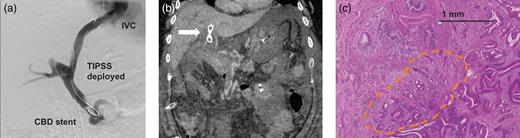

A 49-year-old male with no alcohol history presented to Glasgow Royal Infirmary with a 3-month history of right upper quadrant pain, jaundice, fever and 15 kg weight loss. Abdominal examination revealed hepatosplenomegaly, confirmed by abdominal ultrasound along with intrahepatic biliary tree dilatation. Liver function analysis revealed a mildly elevated bilirubin of 2.05 mg/dl. Computed tomography (CT) imaging demonstrated abrupt distal common bile duct (CBD) narrowing yet normal pancreatic duct. Notably, significant portal hypertension was evident with large para-esophageal varices and splenomegaly (Fig. 1a). With no obvious risk factors for chronic liver disease apart from obesity, alcoholic steatohepatitis was suspected. While magnetic resonance cholangiopancreatography was planned, cholangitis developed, prompting an ERCP, which revealed Grade B esophageal varices, an edematous ampulla (Fig. 1b) and a distal CBD filling defect, which was biopsied, with biliary drainage achieved using a plastic double pigtail stent. Histopathological examination revealed high-grade dysplasia within the bile duct adenoma. With potential for malignant progression, surgical resection was considered; however, comorbidity including obesity and sleep apnea compounded by portosystemic hypertension created a management dilemma.

(a) Preoperative CT scan revealed significant portal hypertension with large para-esophageal varices and splenomegaly. (b) ERCP image demonstrating the ampullary adenoma. (c) Liver biopsy reveals features in keeping with CHF.

Hepatic vein wedge pressure measured 30 mmHg compared to an arterial pressure of 12 mmHg confirmed portal hypertension; however, a fibroscan revealed no evidence of cirrhosis. Prophylactic β-blockers were commenced. Liver histology from a percutaneous biopsy suggested congenital hepatic fibrosis (CHF) as a potential underlying cause of portal hypertension (Fig. 1c). Following intense multidisciplinary discussion, it was decided that in the context of a relatively young, cardiovascularly fit patient with non-cirrhotic liver disease, a TIPS procedure was appropriate, with a view to reconsidering surgery. A literature search failed to identify evidence to support a decision to adopt a staged TIPS with PD for a high-grade dysplastic lesion.